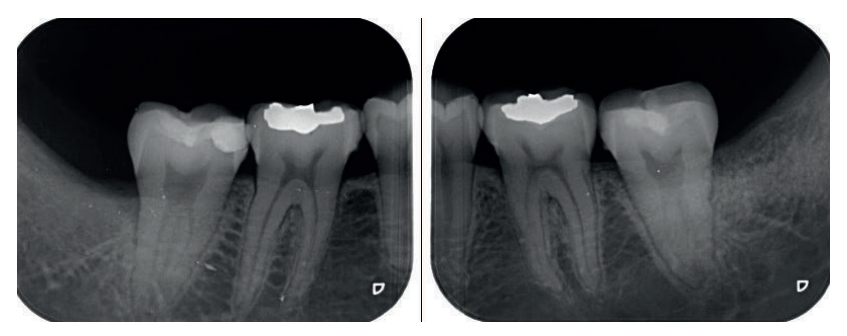

Se retiró la sutura de nuevo a la semana, y se realizaron revisiones a los 3 y 6 meses, donde se midió la profundidad de sondaje (Tabla). Se realizaron radiografías periapicales a los 3 meses (Figura 9) y a los 6 meses (Figura 10).

A los 6 meses se realizó una tomografía computarizada de haz cónico (Figura 11), para calcular la densidad ósea en el lado control (1372,33 Unidades Hounsfield) respecto al lado de estudio (1602,33 Unidades Hounsfield). Además, se comparó la altura a la cresta ósea en el lado control (disminución de 2,1 mm de altura ósea) respecto al lado de estudio (disminución de 0,9 mm de altura ósea).